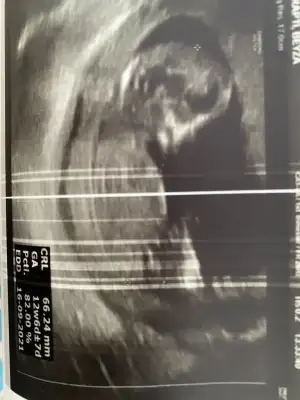

Cnm arkadaşımda tahminde buluna bilirmisin? (vaginal bakilmis) 13. Haftalik

Bu 13. Haftalik vajinal.

10 yada 14. Haftalık varmış birde